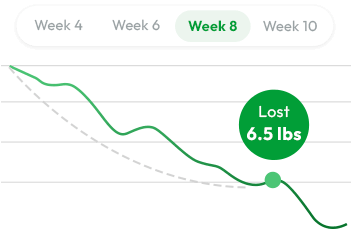

And just recently, Cambridge University researchers confirmed it in a double-blind study.

They found that when this signal is revived using a unique form of resistant starch...

Women lost an average of 6.5 pounds in just 8 weeks without changing anything else.

No calorie counting

No calorie counting No workouts

No workouts Just the signal coming back online

Just the signal coming back online

Study after study.

In a Cambridge-led double-blind, placebo- controlled trial, participants taking RS2 ... a rare resistant starch ... lost an average of 6.5 pounds in just 8 weeks…

Without changing their diet or routine.

And researchers discovered why: RS2 didn't just improve gut health…

It reactivated a hidden fat-command system that controls metabolism at the cellular level.

Without changing anything else about their diet.